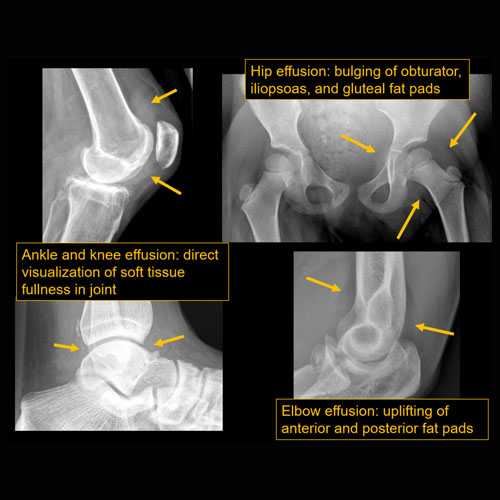

Section 1 Submit Findings CB1119 Findings Findings There are limitations. Yes No There is soft tissue reticulation, fullness, or obscuration of normal fat planes. Yes No There is soft tissue ulceration. Yes No There is soft tissue gas. Yes No There is a foreign body. Yes No There are fractures. Yes No There is periosteal reaction or osseous destruction suggesting osteomyelitis. Yes No There is cloaca, sequestrum, or involucrum. Yes No There is a joint effusion. Yes No There is periarticular osteopenia or erosions to suggest septic arthritis. Yes No There is malalignment, degenerative changes, or other gross internal derangement of the visualized joints. Yes No